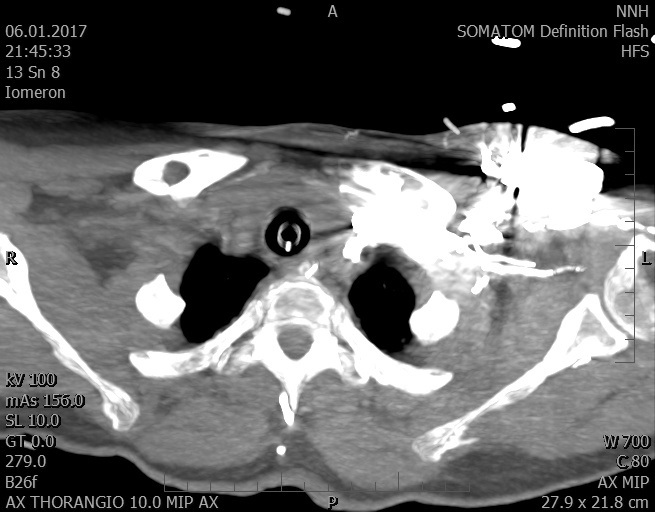

Video 1 - Akutní koronarografie prokázala normální nález na věnčitých tepnách s výjimkou suspekce na lehký spasmus na pravé koronární tepně.Echokardiograficky byla zjištěna těžká dysfunkce dilatované levé komory s nezvětšenou pravou komorou (video 2).

Video 2 - Echokardiograficky byla zjištěna těžká dysfunkce dilatační levé komory s nezvětšenou pravou komorou.Pro nejasnou příčinu zástavy jsme provedli i vyšetření výpočetní tomografií (CT), které vyloučilo plicní embolizaci (série 1 - soubory na konci článku). V den přijetí při přetrvávající oběhové nestabilitě byla nemocná opakovaně defibrilována pro fibrilaci komor se stabilizací rytmu po podání amiodaronu a mesocainu. Dle hemodynamických měření se jednalo o těžký kombinovaný šok. Vstupní laboratorní vyšetření bylo bez větších pozoruhodností. Posléze jsme doplnili anamnézu od příbuzných a zjistili, že pacientka užila do dvou hodin před srdeční zástavou první tabletu amoxicilinu na lehký respirační infekt. Při nevýtěžnosti vstupních vyšetření a nových anamnestických informacích jsme doplnili 14 hodin po kolapsu vyšetření koncentrace tryptázy v séru, která byla extrémně zvýšena (tabulka 2), což nás vedlo k podezření na anafylaxi.